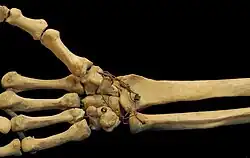

Carpal bones of the hand:

- Proximal: A=Scaphoid, B=Lunate, C=Triquetrum, D=Pisiform

- Distal: E=Trapezium, F=Trapezoid, G=Capitate, H=Hamate

In the hand proper a total of 13 bones form part of the wrist: eight carpal bones—scaphoid, lunate, triquetral, pisiform, trapezium, trapezoid, capitate, and hamate— and five metacarpal bones—the first, second, third, fourth, and fifth metacarpal bones.[8]